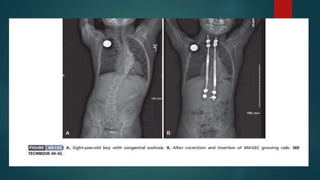

 Growing rods may be used to control curve progression and still allow for

growth of the spine

 This usually requires surgery every 6 months to lengthen the rods

 the use of magnetically controlled growing rods , such as the MAGEC(magnetic

technology with adjustable growing rods and an external remote controller)

spinal bracing and distraction system ,avoids a return to surgery every 6 months

Magnetically controlled growing rods ,such as MAGEC rods,provide a

noninvasive method for rod lengthening,avoiding further surgical procedures